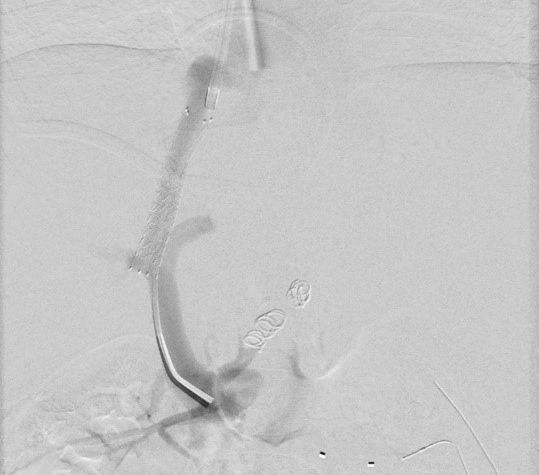

7 jähriger Junge mit Kurzdarmsyndrom und Leberzirrhose

Als Folgen des Pfortaderhochdrucks war die Milz vergrößert (Splenomegalie) und es traten Krampfadern der Speiseröhre (Ösophagusvarizen) auf. Um den Hochdruck zu entlasten wurde ein TIPS angelegt. Dazu wird aus der rechten Lebervene (A) mit einer speziellen Nadel ein Pfortaderast punktiert (B). Anschließend wird die Pfortader mit einem Draht sondiert (C) und die geschaffene Verbindung mit einem Ballon aufgedehnt und anschließend mittels Gefäßstütze (Stent) geschient (D). Durch diese künstliche Verbindung kann das Pfortadersytem deutlich druckentlastet werden.